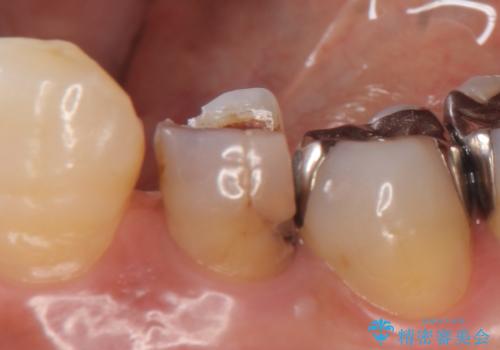

左下4の再根管治療を行い症状が治まったのち、オールセラミッククラウンによる補綴を行いました。

今回用いたオールセラミッククラウンはジルコニアフレームという白い素材の上にセラミックを盛っているため、審美性が非常に高いのが特徴です。

また、ジルコニアは人工ダイヤモンドの材料にも使われているほど高い強度を持っており、そのためオールセラミッククラウンは審美性だけでなく、奥歯やブリッジの補綴も可能とするクラウンです。